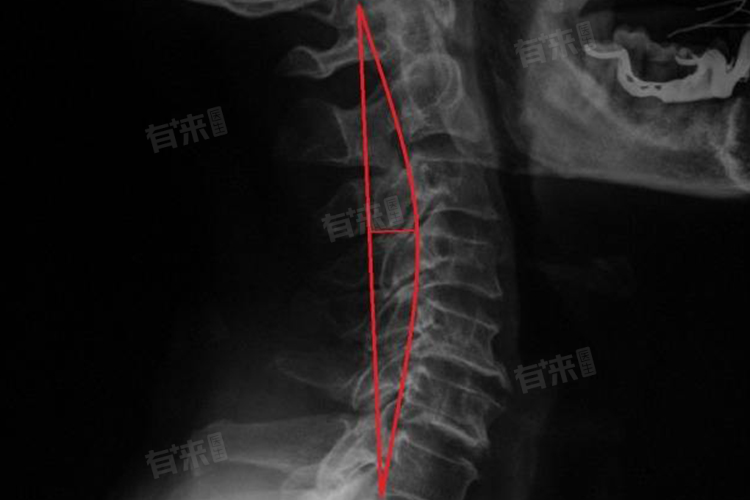

颈椎曲度变直指的是颈椎的正常生理前凸逐渐消失,甚至变为后凸或直线状态,是颈椎结构异常的一种表现,这种情况和多种原因有关,主要包括不良生活习惯、颈椎肌肉劳损、颈椎间盘退变等。